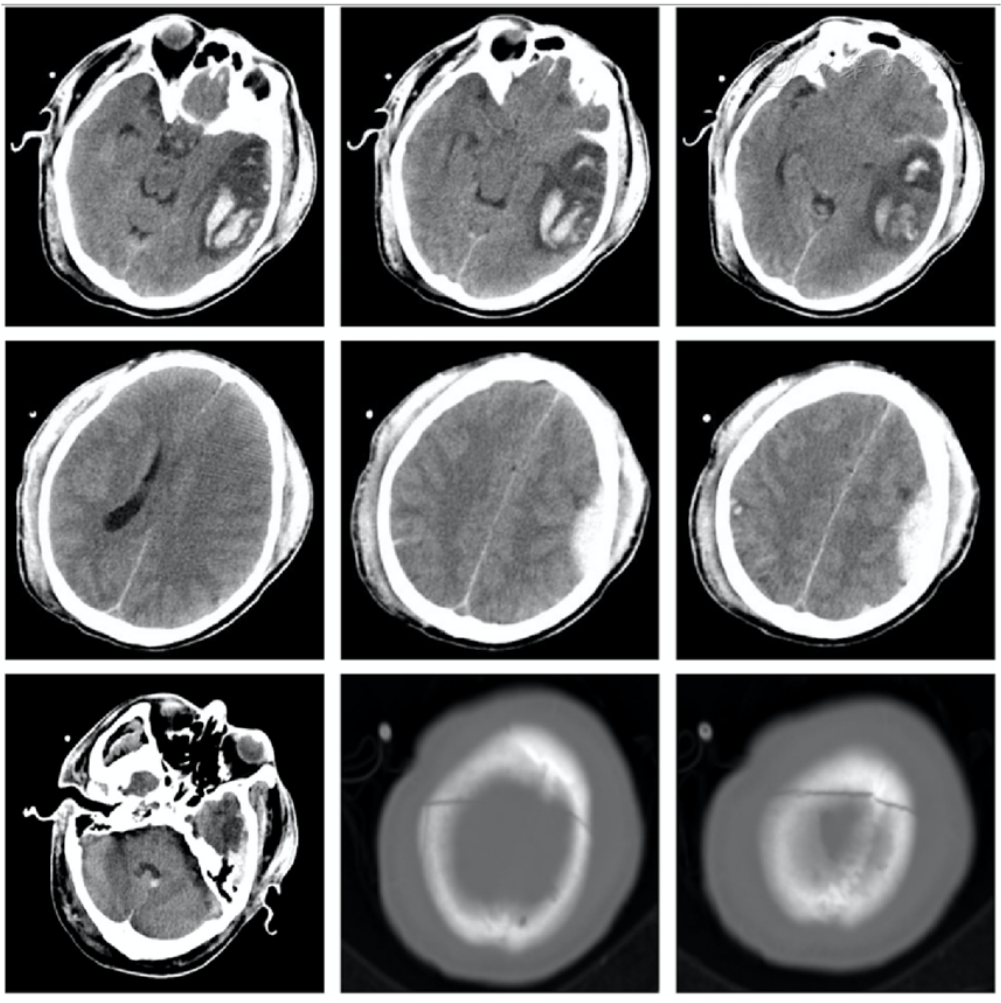

2022年12月15日入院急诊颅脑CT检查结果提示:左颞叶脑挫裂伤伴脑内血肿形成,左侧小脑蚓部血肿,右顶叶脑挫伤,左额颞顶部硬膜外血肿,左额颞顶部硬膜下血肿,蛛网膜下腔出血,双侧顶骨骨折,头皮血肿(图1)肺部CT检查结果提示:双肺多发渗出,下肺不张,双侧胸腔积液,左侧气胸,右侧锁骨中外段骨折,左侧3、7、8、9背肋骨骨折,右侧第5前肋骨皮质扭曲(图2A、B)

图1 患者术前颅脑CT